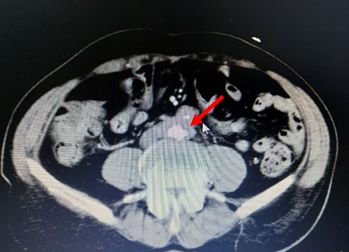

腹部CT检查结果如下:

考虑慢性胰腺炎,脾静脉血栓形成,伴脾门及胃周多发侧枝血管形成,同时合并腹主动脉夹层ⅢB型(Debakey分型),立即严格控制血压在120/80 mmHg一下,同时内科止血、输血后HGB达97 g/L转外科进一步治疗(脾切除术+胃周血管离断术以及腹主动脉支架植入术)。

本例是慢性胰腺炎所致胰源性门脉血栓引起的胰源性门脉高压症同时合并腹主动脉夹层ⅢB型(Debakey分型)。